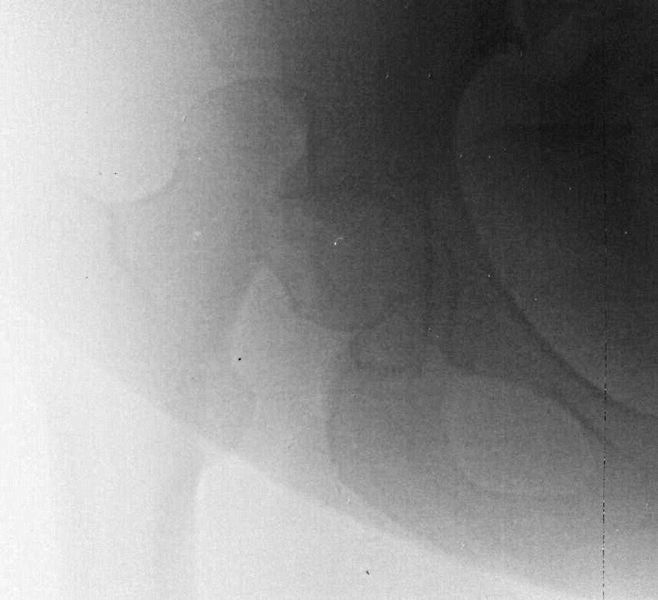

При поступлении выполнено закрытое вправление головки бедра, налажено скелетное вытяжение. Контрольный рентген показал разницу в ширине суставных щелей в сравнении с неповрежденной стороной. Сделали КТ, которое подтвердило наличие внутрисуставного фрагмента задней стенки вертлужной впадины и перелом нижне-медиального сегмента головки со смещением (Pipkin IV).